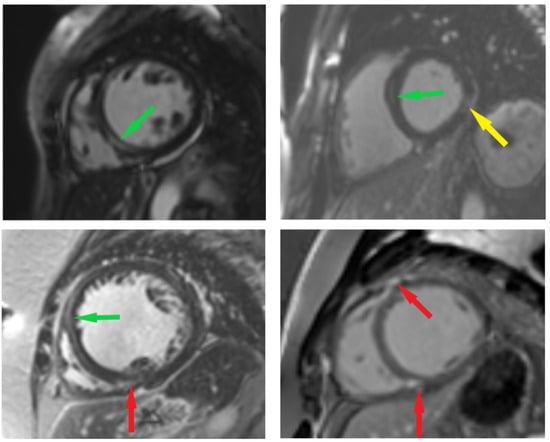

2.4. CMR Imaging Protocol and Analysis